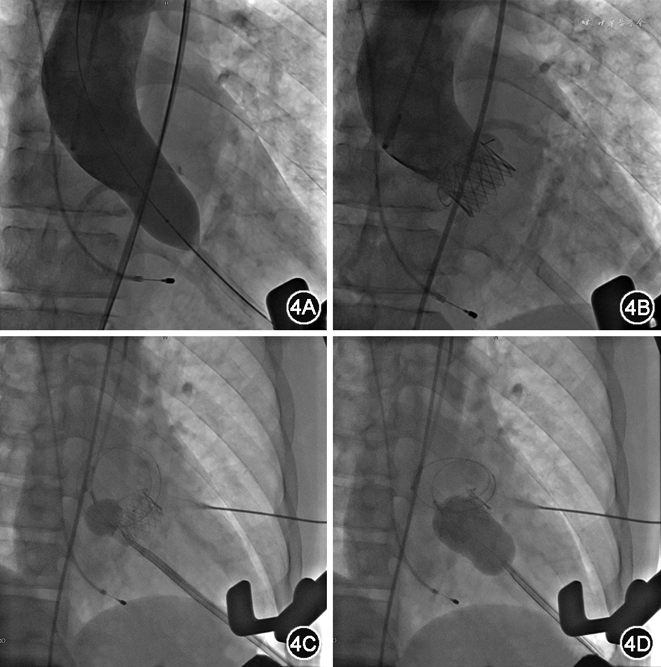

术中透视下取左侧腋前线第6肋间水平开胸,显露心尖后穿刺心尖,逐步交换引入加硬导丝至降主动脉,经心尖送入21 mm J-Valve输送系统,释放支架瓣膜后进行造影及经食道超声行动图检查,提示瓣膜位置满意,未见明显瓣周漏,瓣口流速1.6 m/s,冠状动脉显影良好。再行PBMV,经心尖入路,选用26 mm Inoue球囊(日本Toray Industries Inc.)扩张二尖瓣,术后经食道超声心动图见二尖瓣狭窄明显好转,无明显反流(图4)。